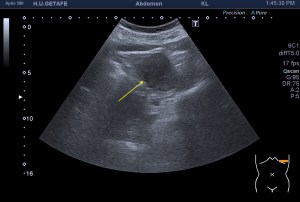

Realizamos una exploración urológica o abdominal normal, de esas que hacemos tantísimas veces…observamos los riñones, llegamos a uno de ellos y observamos esta imagen:

Para quien lleva tiempo dedicado a este mundo de la ecografía esta imagen puede no sorprenderle, pero para quien empieza, como es tu caso, o no tiene muchos riñones vistos, puede asustar. En la imagen 1 y 2 ves un riñón que en su corteza renal, entre ambos polos, una imagen donde apreciamos un aumento del tejido a ese nivel no correspondiente con la normalidad ecográfica de la imagen número 3, que tienes justo debajo y con la que puedes comparar. Dos cortes longitudinales de un riñón izquierdo, escucha, siempre conocedora de la anatomía de la ecoarquitectura que estés estudiando.

¿Qué es lo primero que tenemos que hacer? Lo primero y lo normal es que nos salten las alarmas. Para nosotros un efecto masa en un órgano compacto es una «Línea Roja», es decir, es un límite en el que tenemos que plantarnos y reconocer que eso que tenemos delante en la pantalla puede no ser normal y tenemos que buscar la manera de quedarnos seguras de que lo que estamos visualizando lo es, o no.

En este caso lo primero que tenemos que hacer es discernir entre si lo que tenemos en la pantalla es un tumor o es una hipertrofia de la Columna de Bertin, que por localización, pueden ser perfectamente ambas. Te recomiendo estudiar y documentar perfectamente la ecoarquitectura y una vez que hayas visto bien todo, pongas el doppler color y el modo angio con un objetivo. El objetivo es ver si la lesión está «rechazando vasos», es decir si los vasos se abren no siguiendo la normal vascularización de un riñón. Pasa a las imágenes 4 y 5…